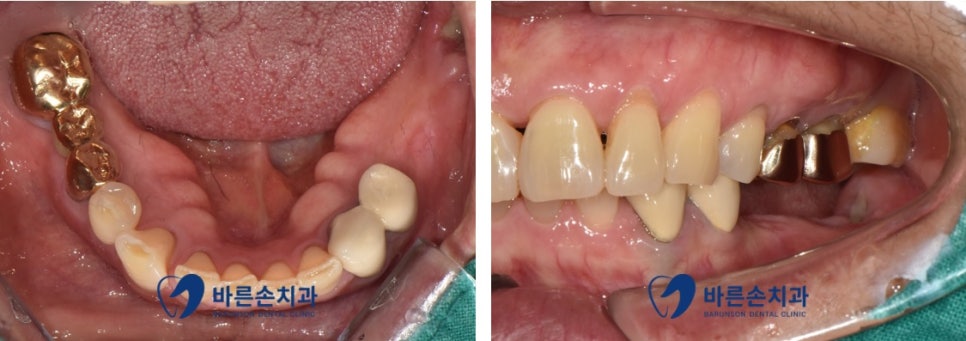

저희 치과에 내원해 주신 환자분의 사진입니다

환자분께서는 오래전에 왼쪽 아래 치아 상실로 인해

식사 시 한쪽으로만 저작을 하다 보니 많은 불편감이 생겨

임플란트 치료를 진행하기로 하였습니다